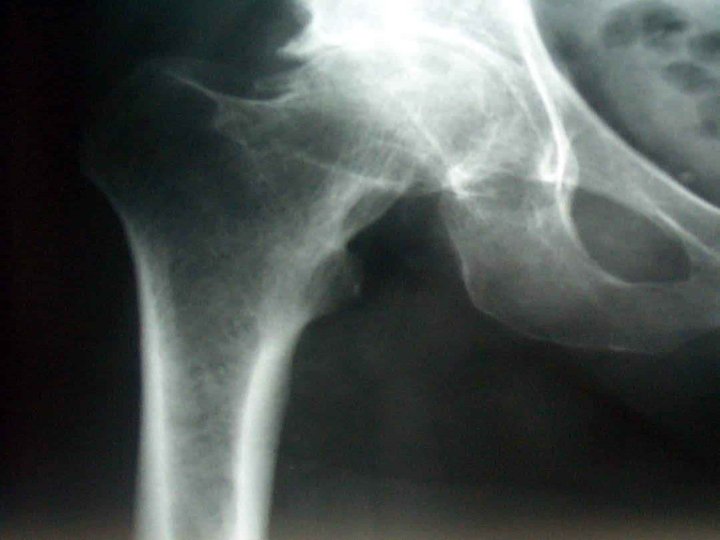

Radiografia Articulações sacroilíacas Coluna vertebral Esclerose óssea perto das superfícies articuladas com anquilose. Erosões nas facetas articulares, ossificação nos corpos, e a coluna adquire a forma de bambu.